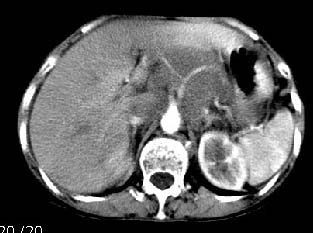

女:61岁.腹痛腹胀20天,行b超腹膜后实性占位.扫完后我查体发现患者右颈根部约3厘米类圆性包块,有移动{我考虑右颈根部包块是肿大淋巴结}.

ct:肝胃之间、胰头后、腹主a周围,融合而成团块状影,包绕血管,胰腺前移后缘分界欠清,与肝胃分界清,肿块未见明显强化,肝右叶后段小囊肿。

女:61岁.腹痛腹胀20天,行b超腹膜后实性占位.扫完后我查体发现患者右颈根部约3厘米类圆性包块,有移动{考虑右颈根部包块是肿大淋巴结}.

诊断:淋巴瘤>转移瘤。

肝胃之间、肝十二指肠韧带,胰头后、腹主a周围,融合而成团块状影,包绕血管[腹腔干、肠系膜上动脉,腹主动脉],胰腺前移后缘分界欠清,与肝胃分界清,肿块未见明显强化,肝右叶后段小囊肿。

主动脉-胰腺间隙可见巨大分叶状软组织肿块影,包绕腹主动脉、腹腔干及其分支、腔静脉等大血管,增强呈无明显强化,临近脏器明显受压移位,增强示有分界。肝右叶可见局限性低密影,边缘清楚。

考虑腹膜后淋巴瘤。